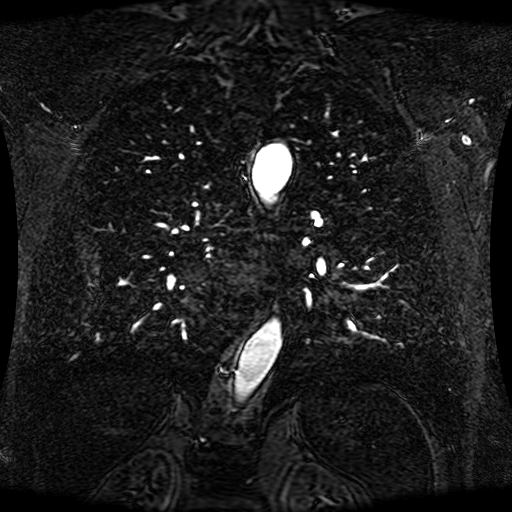

These magnetic resonance angiography (MRA) images show coronal slices acquired from consecutive anteroposterior positions within the torso. The study was performed on a 1.5T General Electric (GE) Signa imaging system with gadolinium-contrast-enhancement for visualization of the cardiopulmonary vasculature. The pulse sequence used was a 3D time-of-flight fast spoiled gradient recalled acquisition in steady state (FSPGR, TR=6.3, TE=1.4, NEX=1, FOV = 40cm, slice thickness = 1.2mm).

This sample image contains 76 frames. It is available in DICOM format (E1154S7I.dcm), as an animated GIF (E1154S7I.gif), as .ogg, .mp4, .webm, and .swf animations (one of which is shown above), or as individual PNG-format frames (see below).